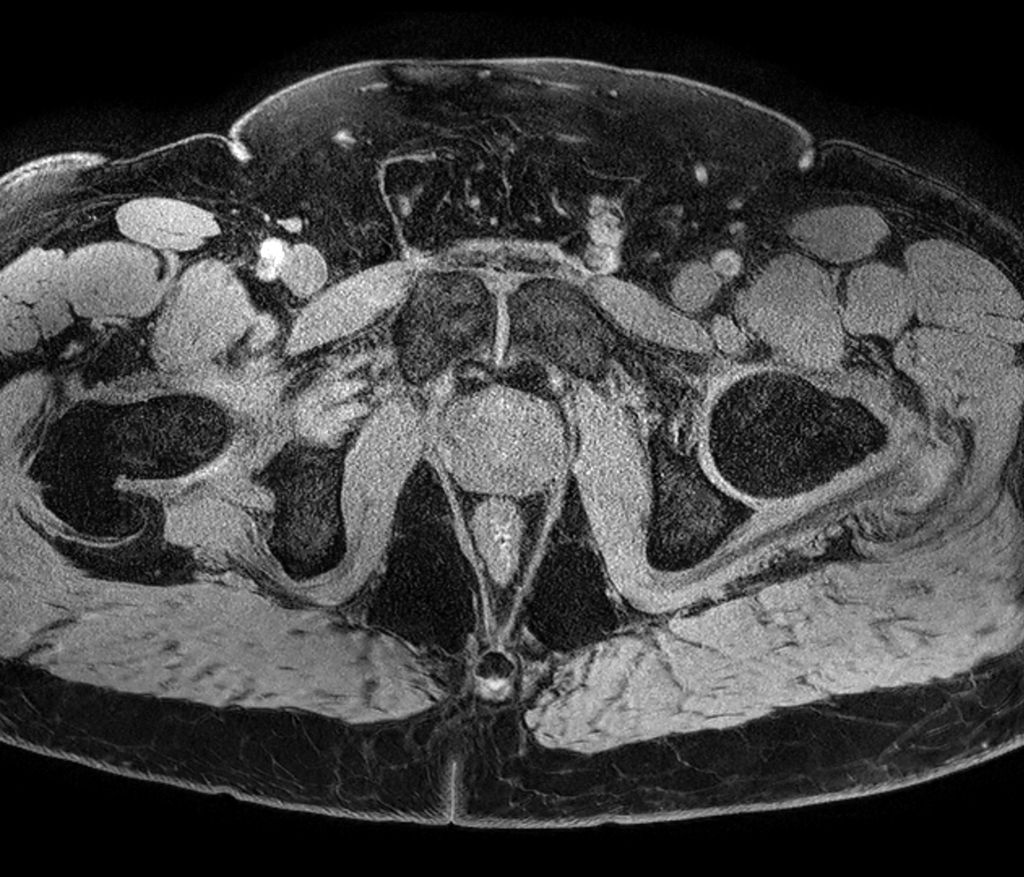

Axial T2w TSE

Axial 3D T2w TSE (PelvisVIEW)

Axial T1w TSE

Coronal T2w TSE

Sagittal T2w TSE